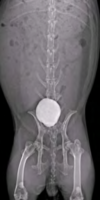

How do you diagnose urinary tract calculi in rabbits?

radiographs or ultrasound

Urinary Tract Calculi:

- Calculi and large amounts of calcium carbonate (urine sludge)

- Signs: calciuria with anorexia, dysuria, stranguria, hunched posture, perineal staining with calcium carbonate precipitate, reluctance to move

- DDx: bladder sludge without calculi, infectious cystitis

- Dx: radiographs or US

- Tx: SQ fluid diuresis, flush bladder (anesthesia) until urine is clear, or cystotomy with culture and stone analysis.

- May commonly recur: increase fluid consumption, change diet to decrease alfalfa (high in Ca2+)